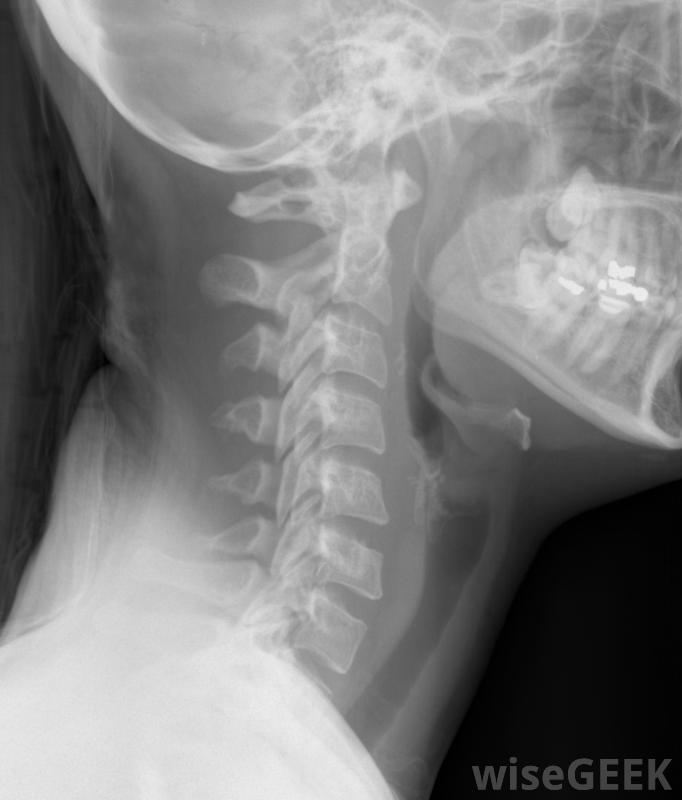

颈部X光片,包括颈椎脊柱的骨头称为椎骨,从颅底向下延伸到骨盆。每根椎骨之间都有小而软的软骨盘,里面充满胶状的核组织。这些椎间盘缓冲着脊椎,颈椎间盘突出防止骨头摩擦并允许灵活的身体运动。椎间盘脱臼时,一个或多个颈椎间盘会从其位置凸出。通常颈椎间盘和脊髓之间存在少量间隙,但严重的颈间盘脱位会使椎间盘压在敏感的脊神经。

颈部脱臼的椎间盘,有时称为滑脱的颈间盘或突出的颈间盘,是指颈部脊柱间的椎间盘破裂。破裂的颈间盘从正常位置突出,压迫脊柱内的神经。视破裂程度而定,椎间盘脱臼引起的颈部疼痛可能从中度到重度不等。 颈部X光片,包括颈椎...